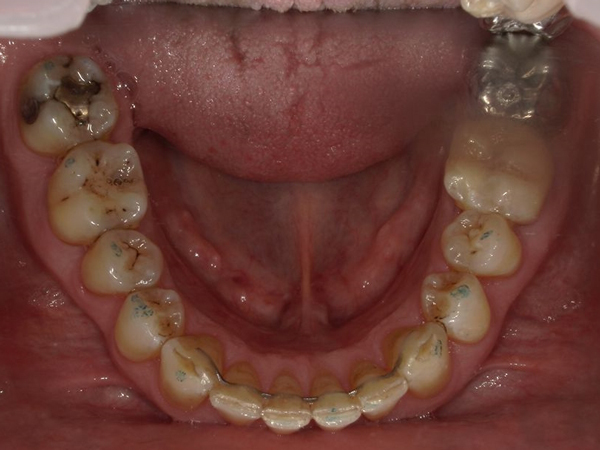

Arcade mandibulaire avant traitement orthodontique, séquelles de maladie parodontale